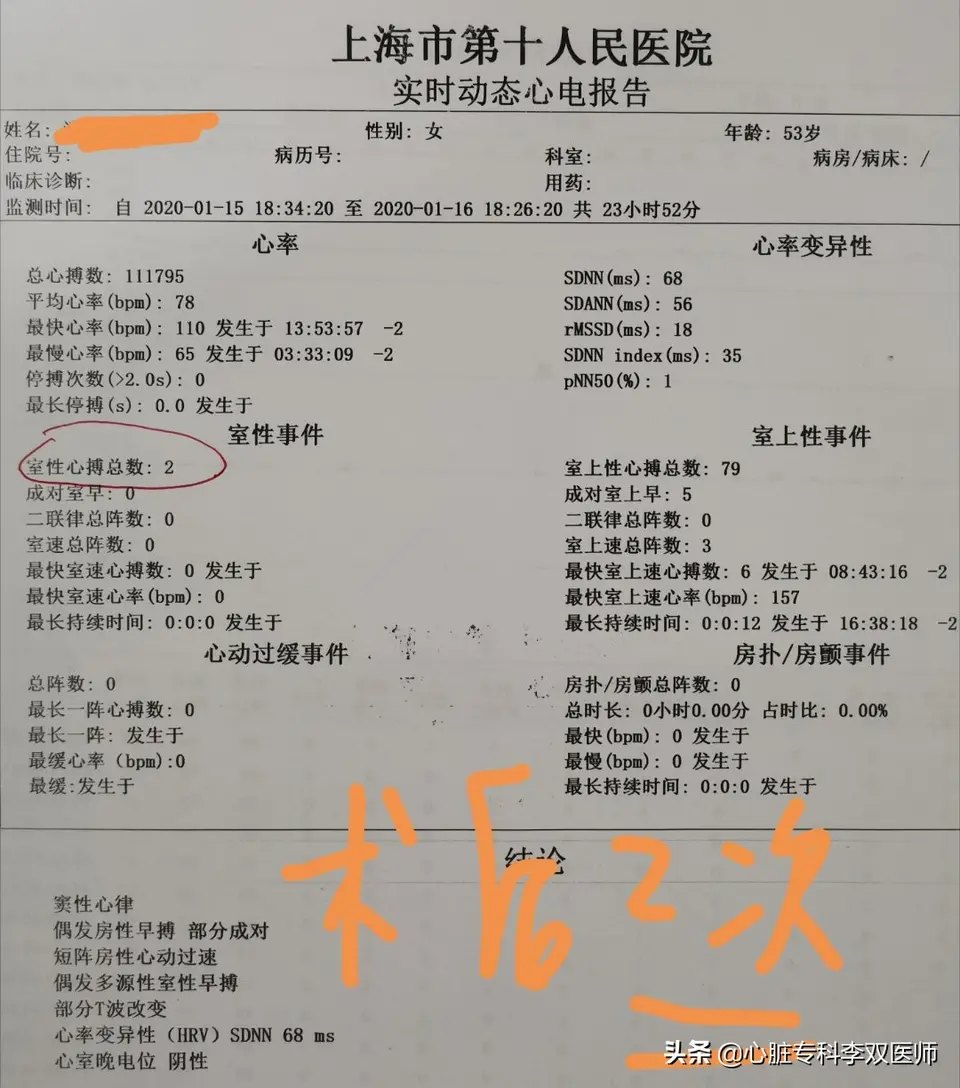

前天给一个外地来就诊的病人做了难度很高的“心外膜室早”消融的病例,病人一年前在杭州某三甲医院曾行消融失败,这一年来因为笼罩在“频发室早”的阴影下,患者有了明显的心理问题。这次我们标测的情况和上次外院消融情况完全一致,只是坚持又带有一点运气的在非传统的消融位置(解剖位置,而不是最早激动位置)尝试了消融,结果异常的顺利,术中忐忐忑忑观察了一小时无复发。今天患者顺利出院,术后24小时心电图提示的室早仅2次(一天的心跳是约10万次,1000次以内的早博没有意义),比机器的误差都小,而术前是1.4—2.8万次,是万!万!万!。坚持就是胜利,坚持带来好运!